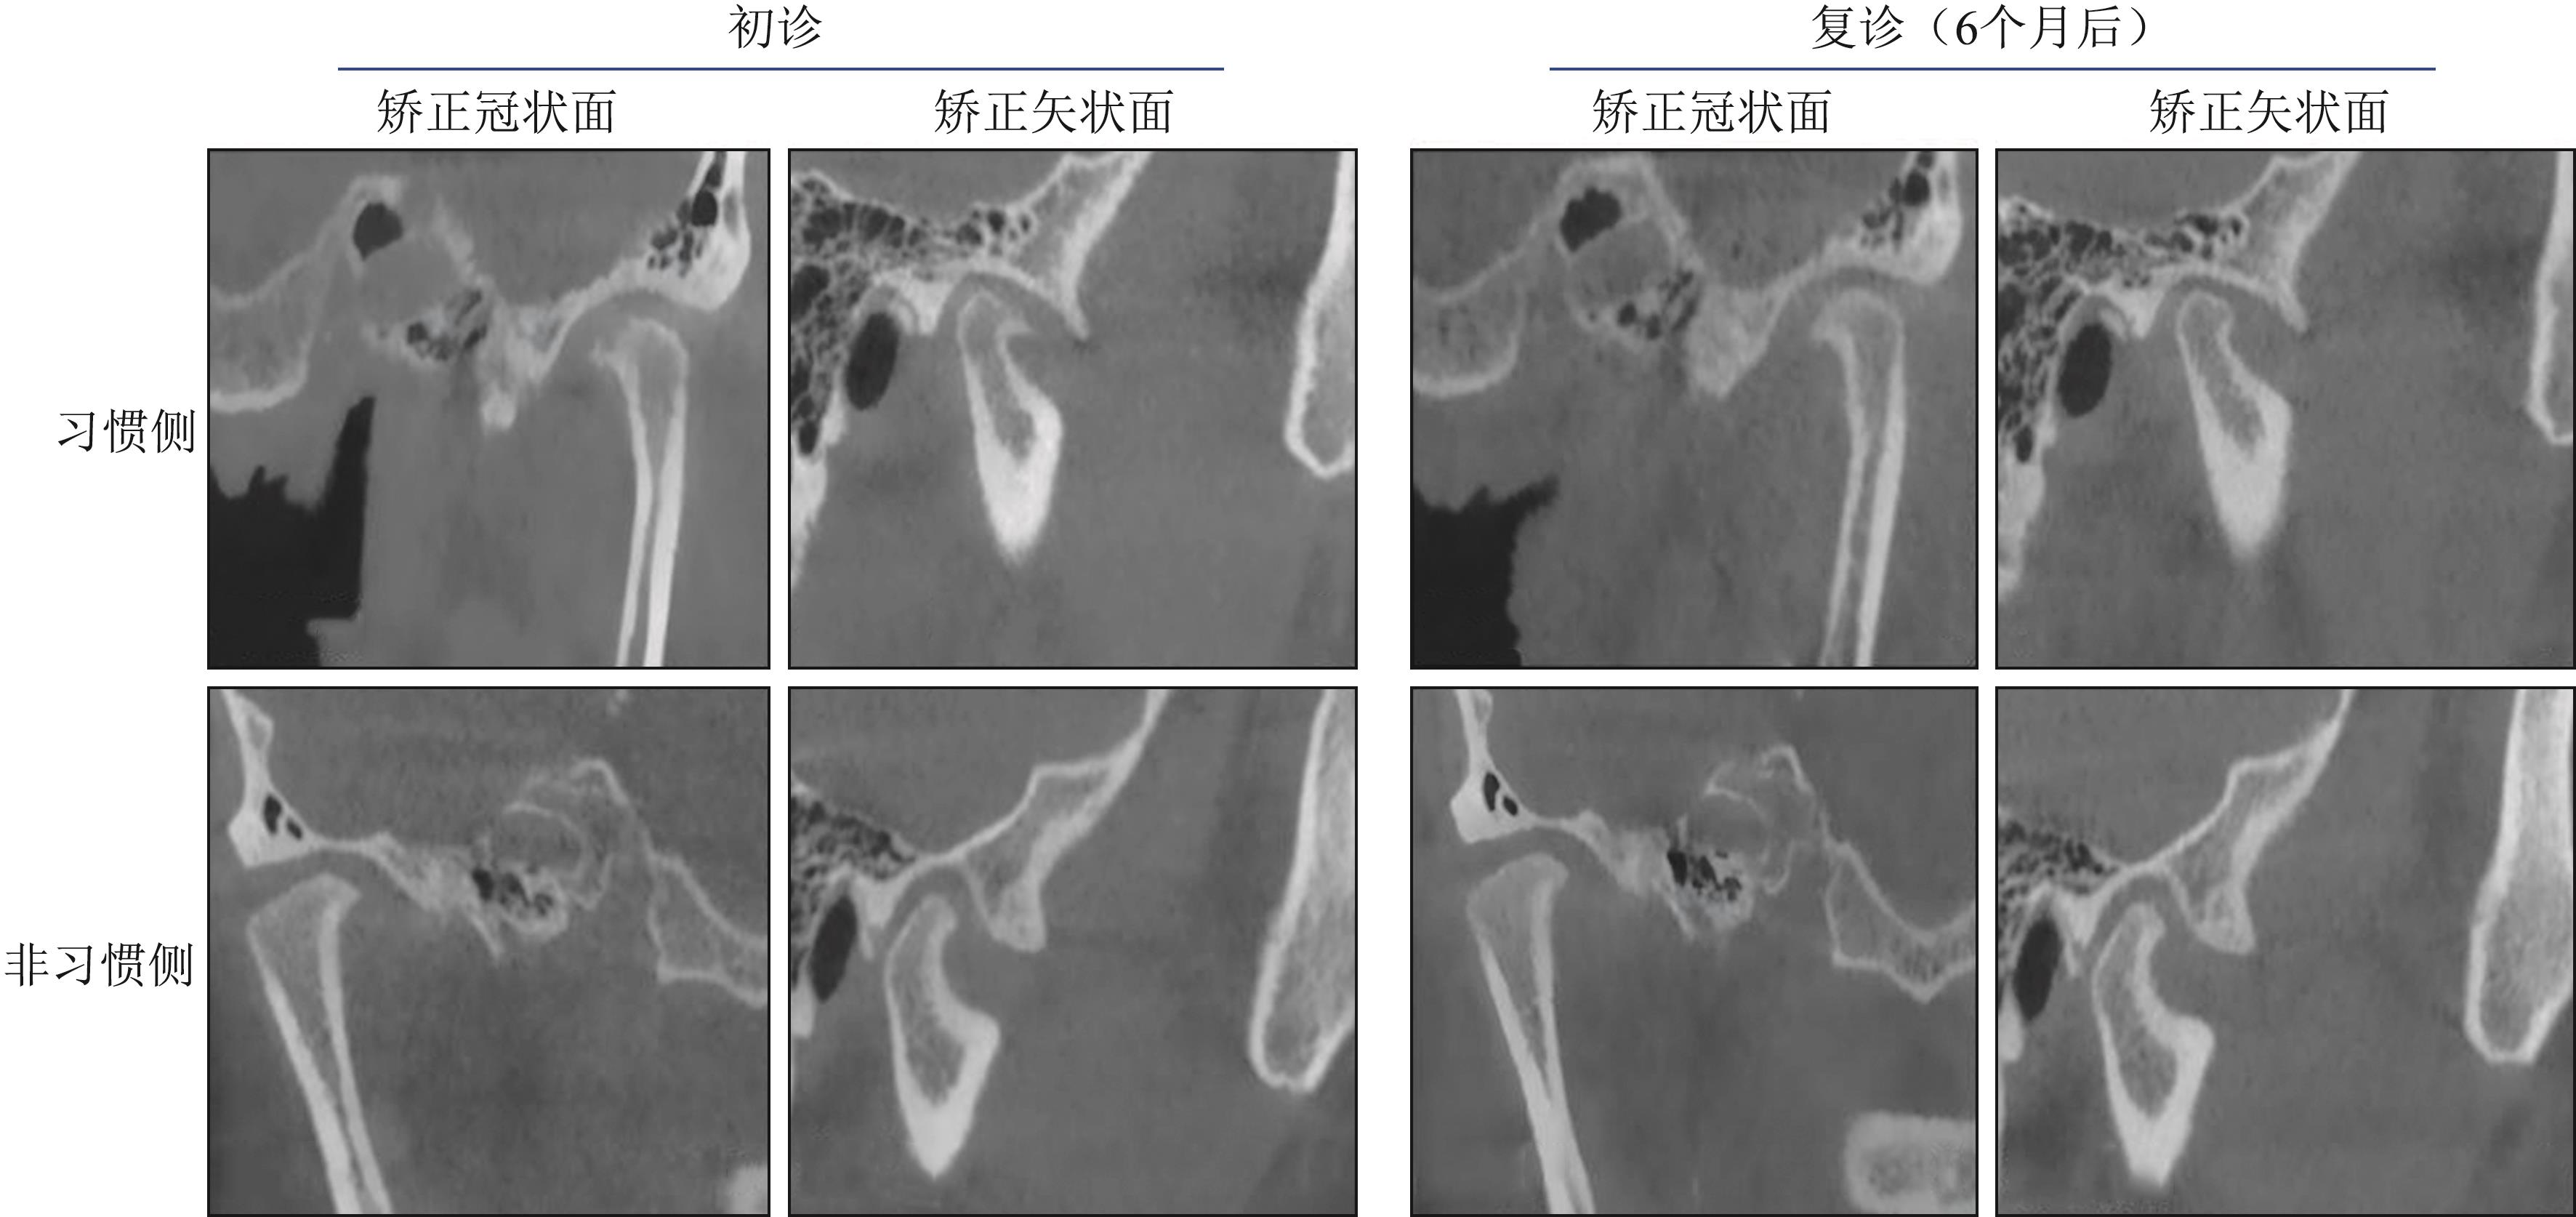

李晓星, 马博文, 徐鑫宇, 等. 伴偏侧咀嚼颞下颌关节骨关节炎患者1年随访的CBCT研究[J]. 口腔颌面修复学杂志, 2025, 26(1): 42-49.

|

Li XX, Ma BW, Xu XY, et al. CBCT study of patients with temporomandibular joint osteoarthritis accompanied by lateral chewing for 1 year follow-up[J]. Chin J Prosthodont, 2025, 26(1): 42-49.